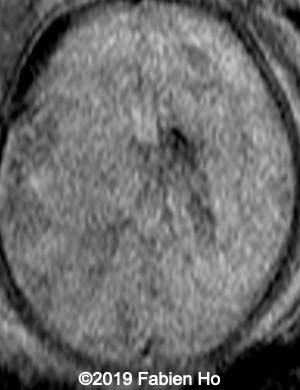

Axial DWI (diffusion weighted imaging): DWI is sensitive to cytotoxic cell edema, found in brain ischemia, among other things.

10

11

Images 4-11, fetal brain MRI at 28 weeks: the left frontal lesion hence shows DWI hyperintensity, with T2* and T1 peripheral hyperintensity: ischemia with peripheral subacute hemorrhage. Note also that there is an associated blood clot in the left lateral ventricle. There is no obvious mass effect, nor peripheral edema. All these findin>gs are very suggestive of a clastic lesion.